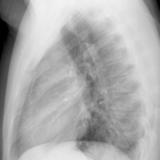

Thymic carcinoma Lat

Date: 08/15/2012

Views: 10111